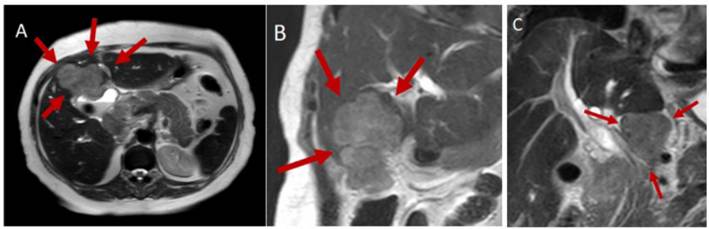

| Imagen 5.- Resonancia magnética que muestra gran masa en la vesícula biliar con infiltración al hígado (A y B) y conglomerado ganglionar celíaco (C). |